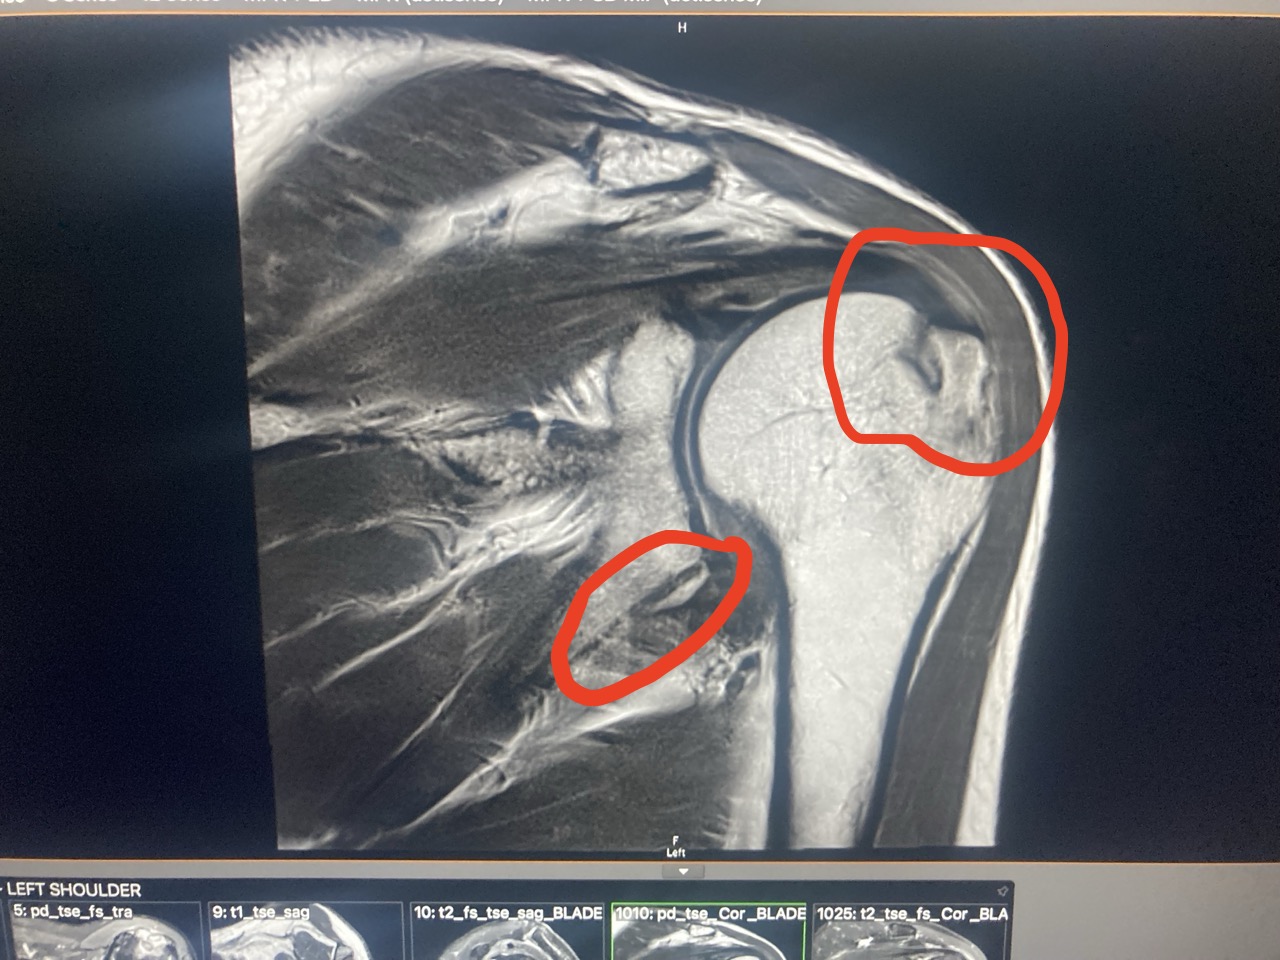

The surgeon was great and was probably more excited about my trip than my shoulder. As was the physio. I think most of their patients my age have a fall and break stuff. Not get hit by a bus while riding a motorbike in Venezuela. His diagnosis. He said the main problem was that I had Post Traumatic Frozen Shoulder. My arm and shoulder had made a pact to never allow anything like that to happen again and had just locked up and it would take 12 to 18 months to regain full movement again. He said I had broken a piece off the end the ball of my arm and a piece of the bottom of the socket that it sits in. His recommendation was that it was healing well and that I didn’t really need surgery. He suggested getting a Hydrodilation injection under a CAT scan and have physiotherapy. And be patient. I did get the injection, and while it didn’t give me much more movement, it did take the pressure off and took the constant pain away which I was grateful for.